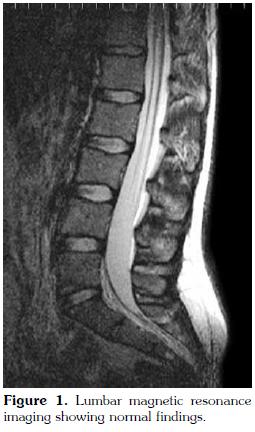

There were no abnormal findings of the lumbar spine on magnetic resonance imaging (MRI) (Figure 1). Contrast enhanced sacroiliac MRI revealed lobulated, multivesicular cystic lesions, which originated from the second sacral vertebra, extending to the sacral ala and iliac wing at the third sacral level, which also filled the sacroiliac joint. Vesicular lesions in the sacroiliac joint and piriform muscles showed increased contrast uptake (Figure 2). Given the patient's medical history, bone hydatid disease and other cystic bone lesions were included in differential diagnosis.

Furthermore, MRI usually helps to define features of the cyst except calcifications.[4] Hydatid cyst appears as well formed, thin-walled and spherical lesions on MRI.[10] The fluid of the cyst is isointense with cerebrospinal fluid both on T1 and T2-weighted images and the wall of the cyst appears as a low signal intensity rim. In defining the wall of the cyst, T2-weighted images are superior to T1-weighted images. Fluid has a high signal intensity and, in contrast, the wall of the cyst has a low signal intensity on T2-weighted images.[1] After intravenous contrast agent administration, the rim of the cyst shows no uptake. Calcification of the cysts wall is a very rare entity.[11] Computed tomography images resemble T1-weighted MRI images. Magnetic resonance imaging of our patient revealed characteristics of hydatid cyst. Regular, thin-walled cyst and pericystic contrast uptake was determined. Chronic osteomyelitis, fibrous dysplasia of bone osteosarcoma, benign cystic lesions of the bone, brown tumor (hyperparathyroidism), and neoplastic lesions all should be included in the differential diagnosis.[12,13] Localization of lesions is also important. Although our patient did not present with inflammatory back pain, she had a presumptive diagnosis of AS and was medically treated for two years. This caused a delay in the diagnosis and unnecessary use of medication. Hence, atypical presentation of hip or low back pain and its irresponsiveness to anti-inflammatory medication warrants further investigation.